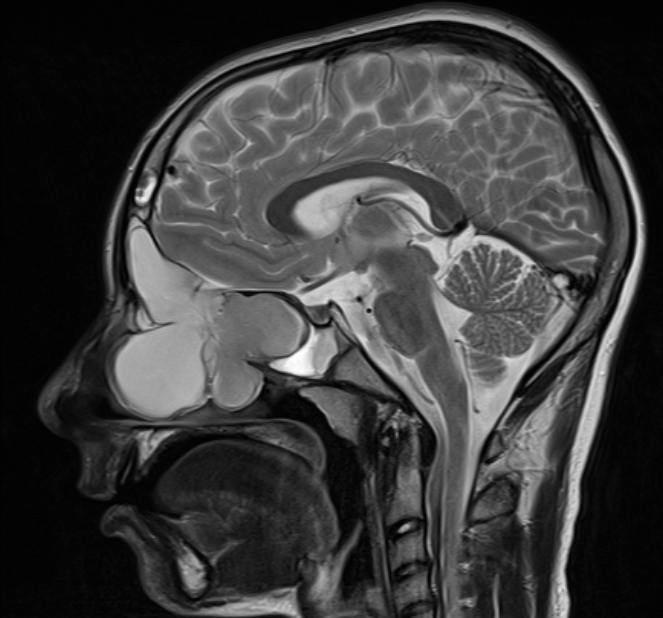

FIGURE 31-5 Basal encephalocele.A, A sagittal T1-weighted image shows callosal agenesis with a tiny lipoma (arrow). A large defect in the basisphenoid is seen. Note the apparent absence of the pituitary, floor of the third ventricle, and optic pathways. B, A high-resolution sagittal T2-weighted image shows the pituitary-hypothalamic structures (arrow) and optic pathways are contained within the encephalocele.